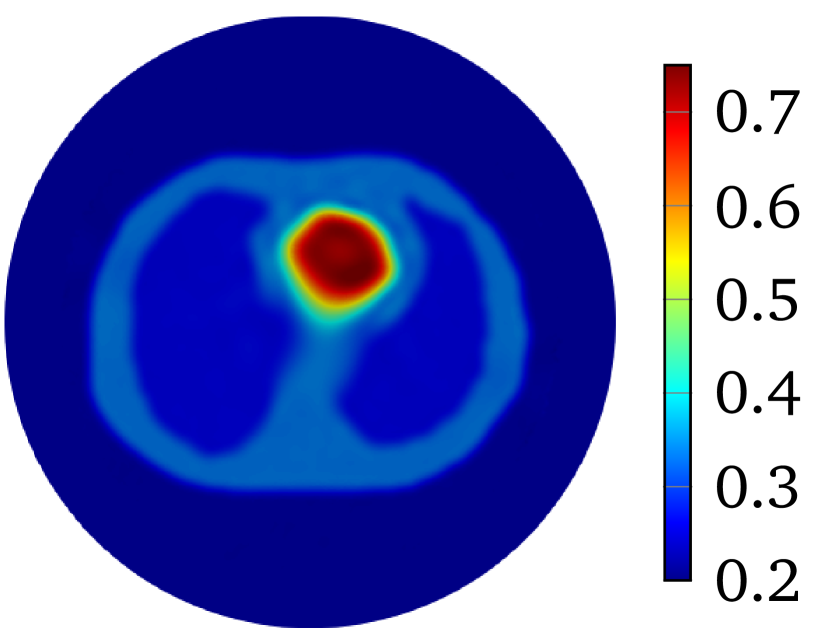

The LM-SCEM algorithm is used to reconstruct the distribution of . The initial guess is given as which is the value of the background tissue. The conductivity in the region for is supposed to be known. The values of are truncated to only update for with . The discontinuity caused by this truncation can be removed by applying (20) properly (either by mollification or simply by replacing the discontinuous values), but it does not cause any numerical problems since is small, so no special treatment was done in the following computation. The values of for the first 15 iterations are shown in Figure 4(a). The relative error is also given in Figure 4(b). With noise, the reconstruction with uniformly converges to with 15 iterations. The reconstructed is shown in Figure 5(a). To achieve a level of , it takes more than 40 iterations. A reconstruction with and is then carried out, but a similar speed of convergence and relative error is observed, result is in Figure 5(b). When the current pattern is further considered into the reconstruction, an obvious improvement of convergence is seen, and a relative error level is achieved with 14 iterations, the conductivity map is shown in Figure 5(c). Therefore, the convergence of LM-SCEM depends not only on the regularization parameter and the scaling parameter , but also on the current patterns for the measurements. Since indicates 0.1% of Gaussian noise in the simulated , the reconstructed result with is already good, and more iterations will not improve the result. To verify, a reconstruction with , and is carried out with (1% noise). Relative errors are shown in Figure 4(b), the reconstruction converges to within 7 iterations, and more iterations did not bring any improvements. The reconstructed result is given in Figure 5(d).